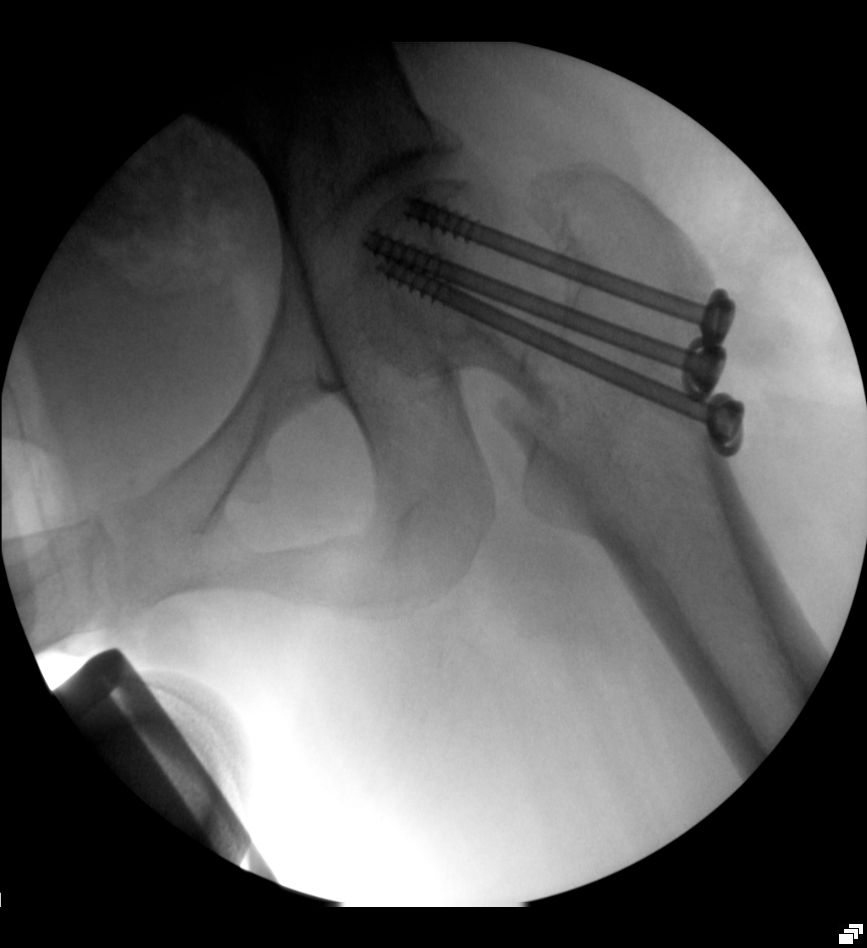

| Notfallmäßige Versorgung mit 3 Schrauben | ![]() | |

| Versorgung mit 3 Schrauben, Kontrolle | ![]() | |